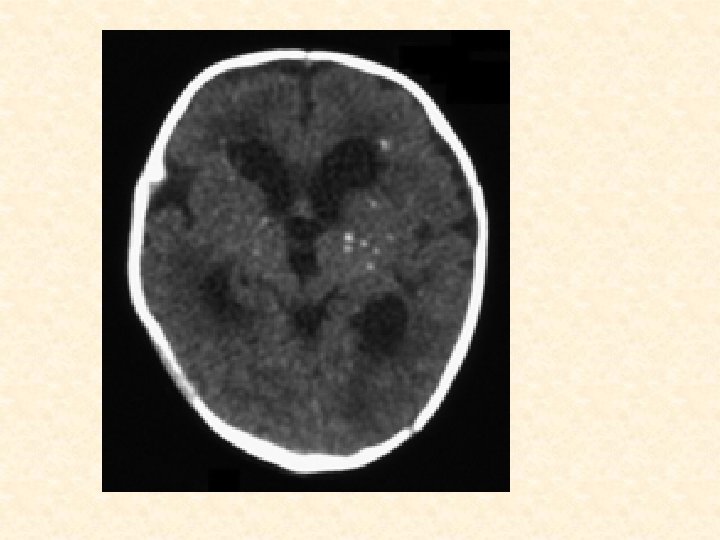

Investigation • Isolation of T. gondii from placenta or cord blood • Serology • measures Ig. G T. gondii antibody • Ig. M antibody test • Imaging Studies • CT (Head) – intracranial calcifications(scattered through the brain tissue)